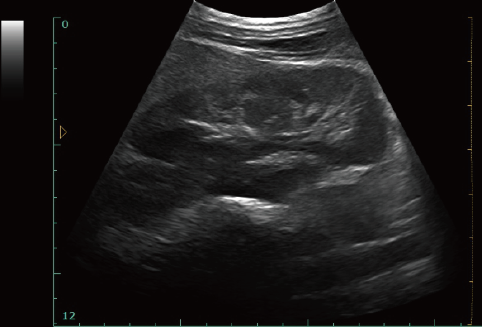

12 Inch LED Diagnostic Medical Ultrasound Laptop Ultrasound Scanner With One Probe Connect Vet Software Available

12 Inch LED Diagnostic Medical Ultrasound Laptop Ultrasound Scanner With One Probe Connect Vet Software Available Images |